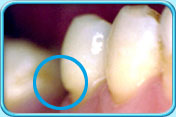

图中所见是蛀坏的牙齿补牙前的外貌。补牙前